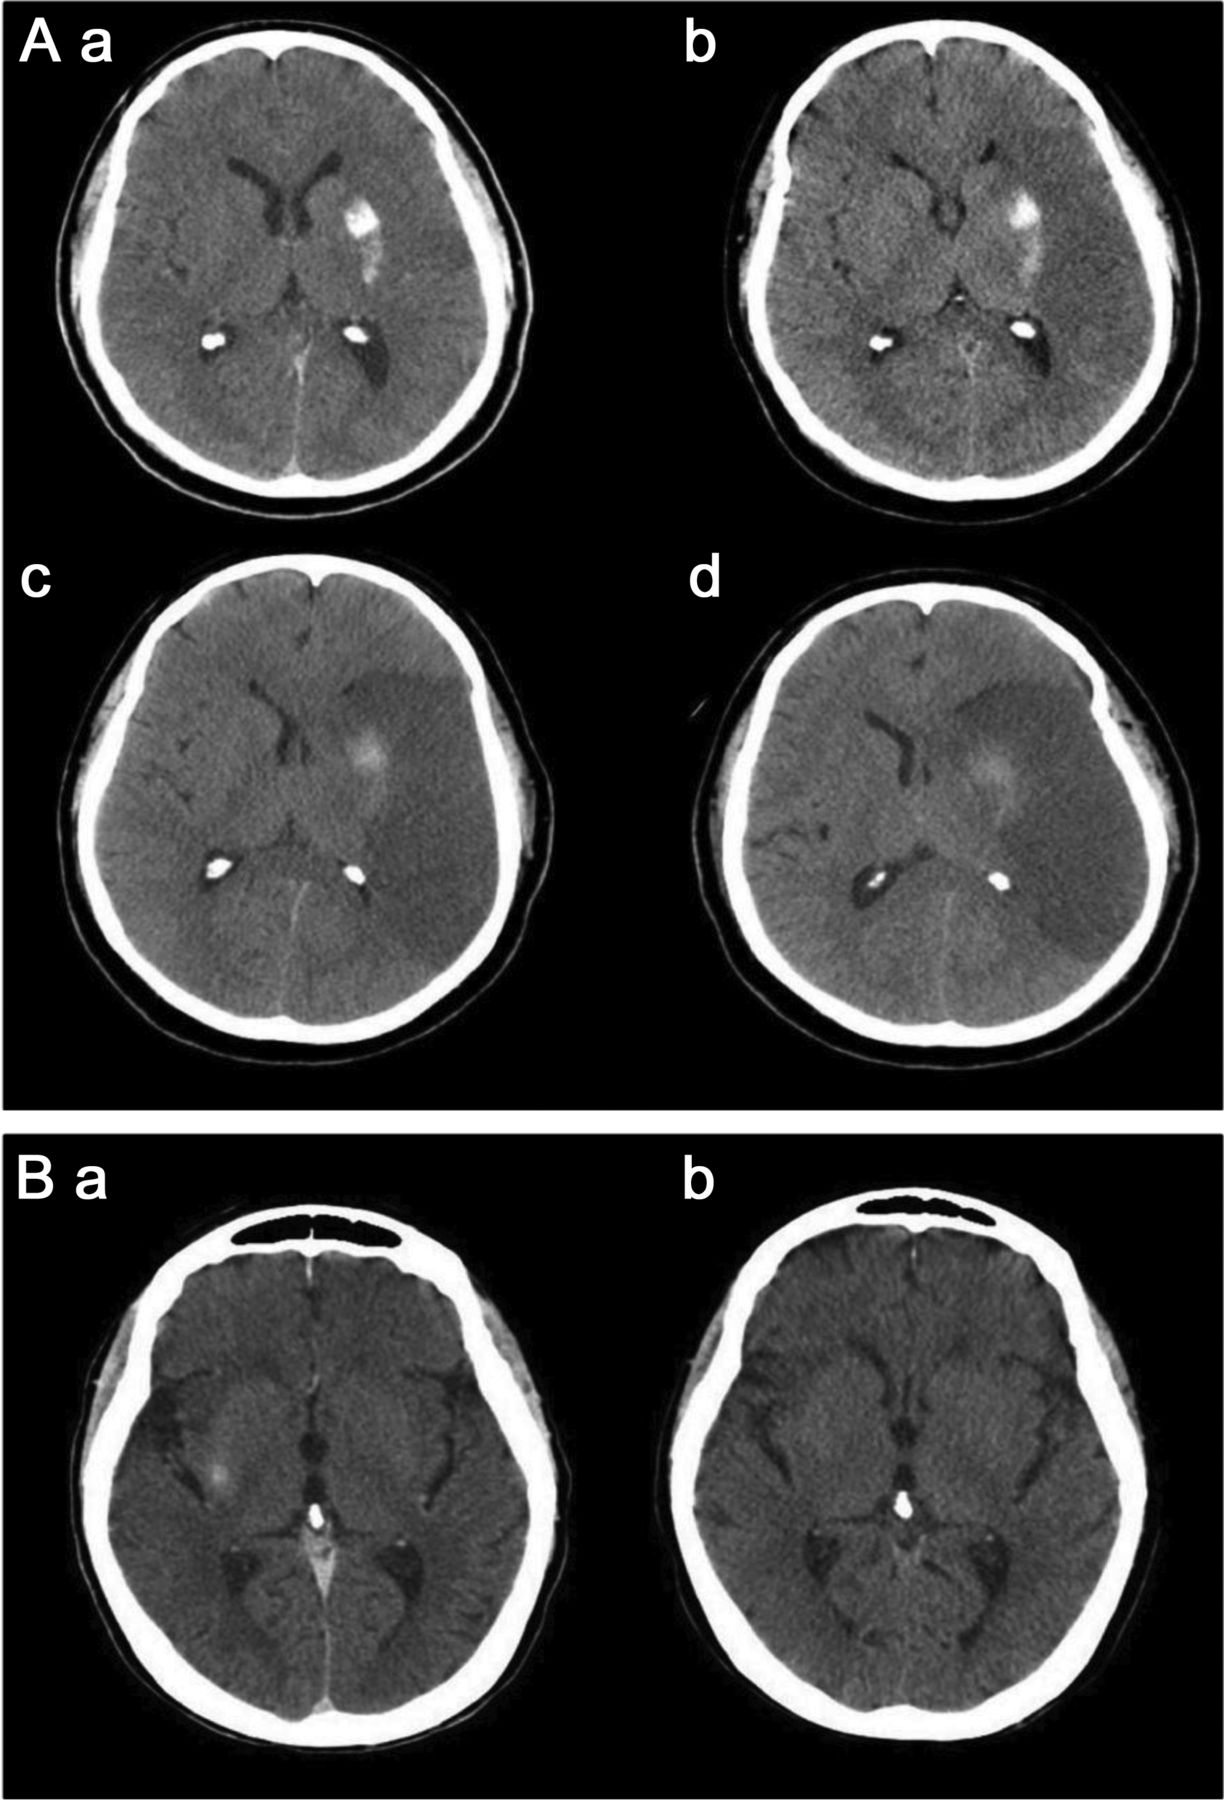

一位39岁的女性接受了左颈内动脉(ICA)血脑屏障破坏(BBBD) (A),与(预期)合成左半球皮质增强超声造影CT(摄影)(B,虚线箭头),可能有轻度左侧皮质增强大脑后动脉(PCA)分布,有一个著名的离开沟通后动脉供应左侧PCA(点划轮廓,B)。Postcontrast t1加权磁共振成像(C)显示,病灶增强,对应于这些可视化post-BBBD摄影(实心箭头,B, C),与适量的右额叶病灶周围水肿和证据传遍的胼胝体膝fluid-attenuated反转恢复核磁共振(D)。